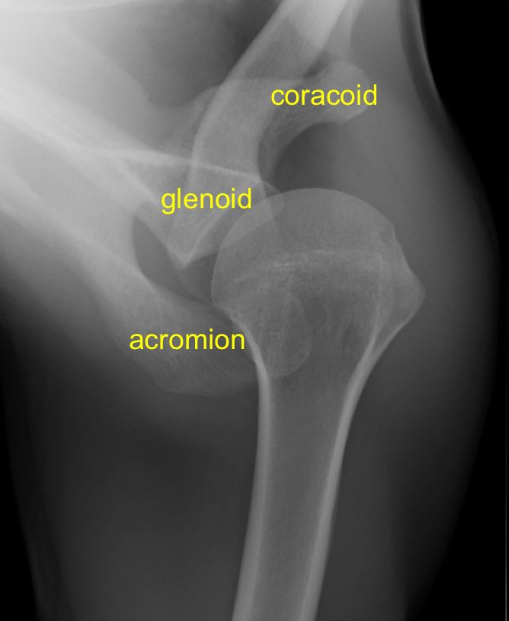

안녕하세요, 오늘은 어깨(shoulder) 촬영방법 중 하나인 superiorinferior axial 촬영법에 대해서 설명하겠습니다. 이 촬영법은 proximal humerus(상완골 근위부)와 glenoid cavity(관절와)를 관찰하기 용이합니다. ac joint(견쇄관절), coracoid process(오훼돌기), subscapularis(견갑골하근), teres minor(소원근)의 바깥부분이 보입니다. 그럼 이미지와 함께 설명 시작하겠습니다.

- Glenoidhumeral joint(상완와관절)가 잘 보여야 한다

- acromioclavicular joint(AC joint, 견쇄관절)이 잘 보여야 한다.

- lesser tubercle(소결절)의 측면상이 보여야 한다.